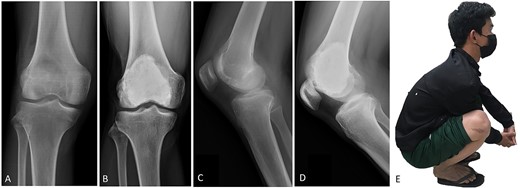

(A, C) Case no. 6: male, 15 years of age with GCTB at the distal femur without subchondral bone involvement, Campanacci grade II. (B, D) Radiograph at 67 months after extended curettage with hydrogen peroxide, phenol, and cementation. (E) MSTS score 100%.